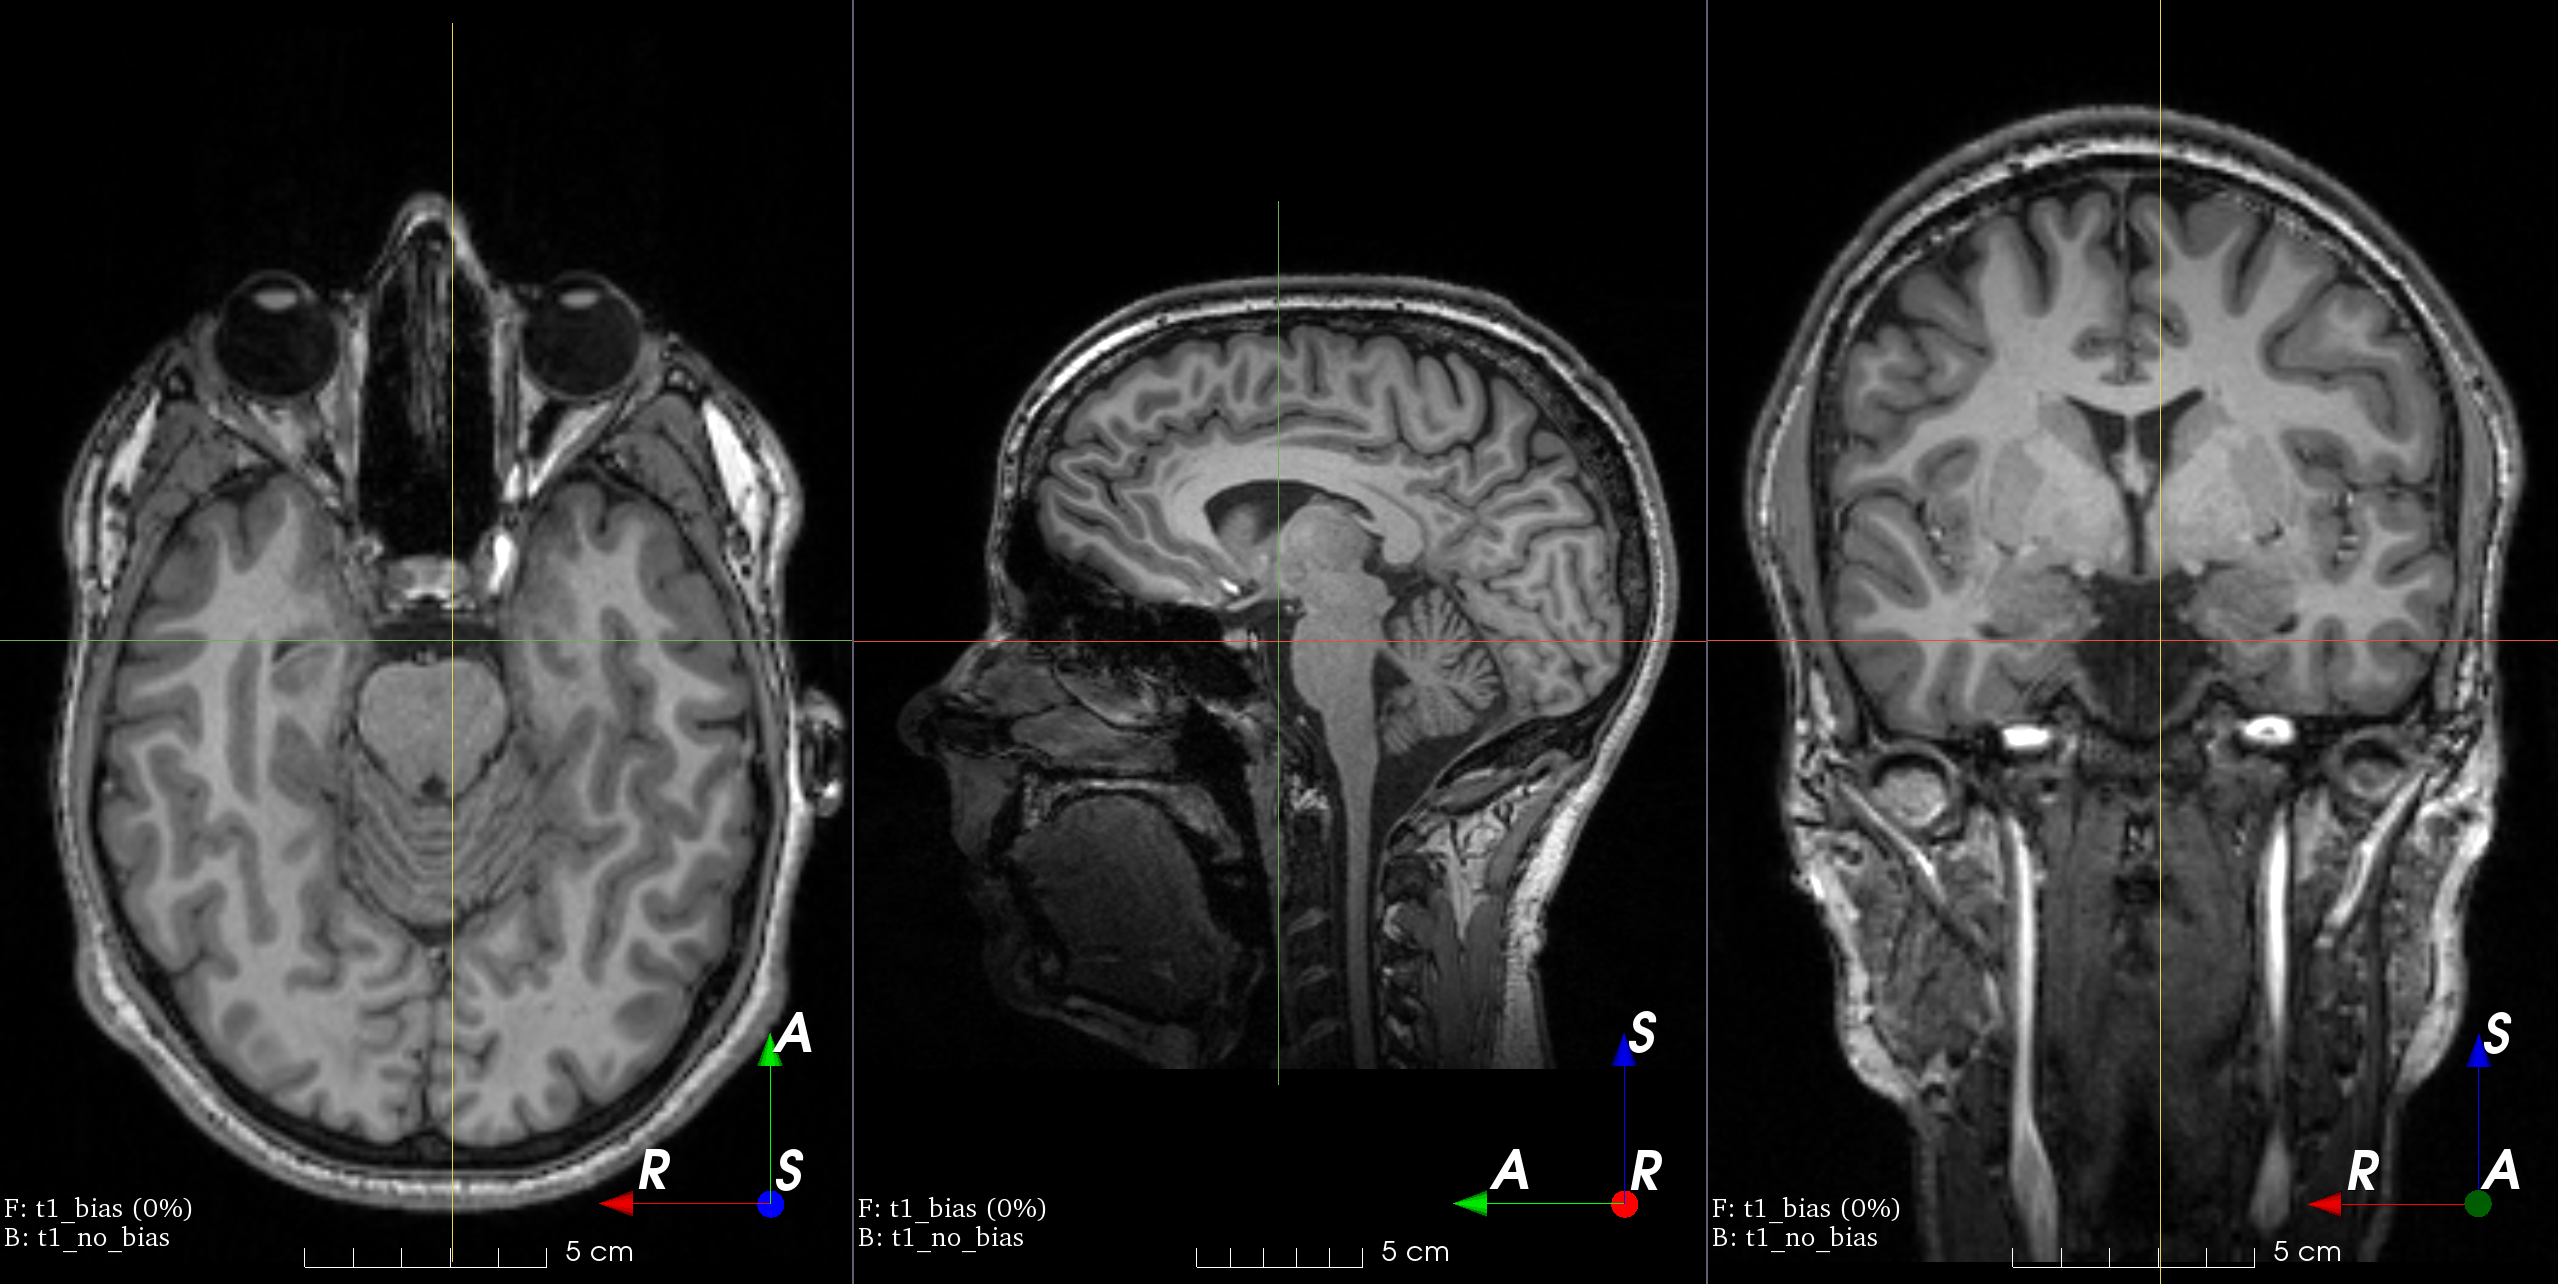

Add random MRI bias field artifact.

MRI magnetic field inhomogeneity creates intensity variations of very low frequency across the whole image.

The bias field is modeled as a linear combination of polynomial basis functions, as in K. Van Leemput et al., 1999, Automated model-based tissue classification of MR images of the brain.